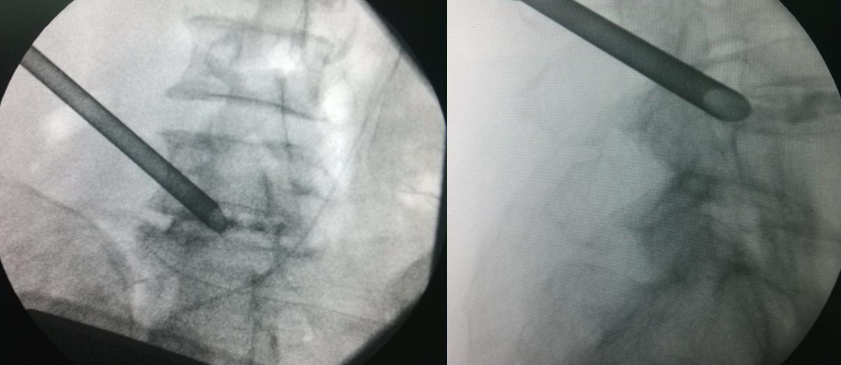

使用骨钻时,用C型臂从前后和侧面确定器械和骨钻顶端的位置。骨钻的最前端不能超过中线,以避免刺激或损伤神经。

用C型臂确定工作套管放置的位置。正确的位置应该是放在神经根下方,椎间盘水平,顶端正好在中线,开口朝向突出的髓核。